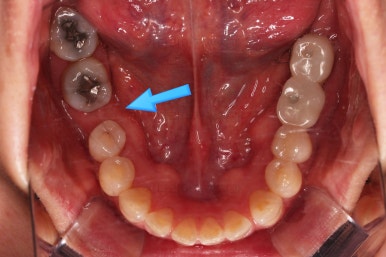

점점 공간이 어금니 크기로 회복되고 있는 것이 보일거에요.

단순히 쓰러진 어금니를 뒤로 밀기만 하는 것이 아니라 안밖의 위치, 회전 양상, 높낮이 등도 정교하게 조절을 합니다.

X-ray 사진으로 중간평가 해주고요.

적절한 자리가 마련되었다고 판단되면 임플란트 식립 가능성을 평가하게 됩니다.